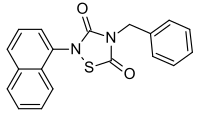

Tideglusib

| Formula | C19H14N2O2S |

| Molar mass | 334.39 g·mol−1 |

Tideglusib (NP-12, NP031112) is a potent and irreversible[1] small molecule glycogen synthase kinase 3 (GSK-3) inhibitor.[2]